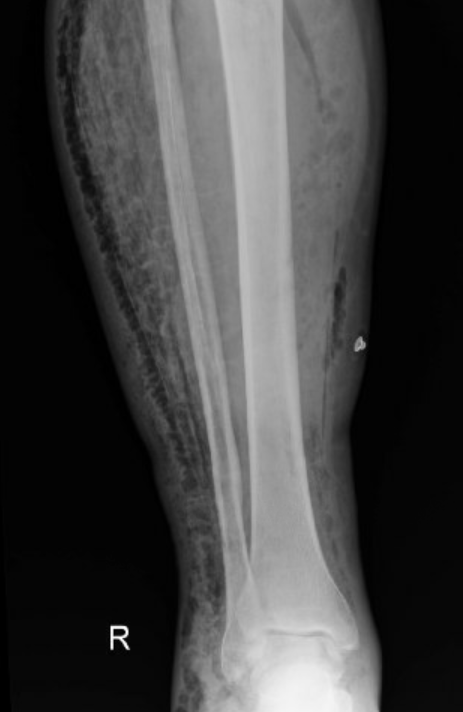

Below is a case of extensive right lower extremity necrotizing fascitis with diffuse subcutaneous emphysema.

Right tib/fib: